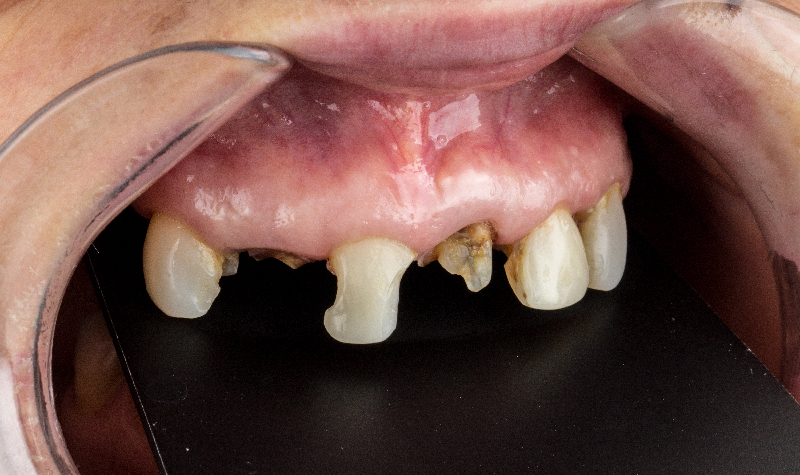

Rehabilitación oral total con prótesis inferior sobre implantes y coronas superiores.

Prótesis híbrida inferior de cerámica fija sobre implantes.